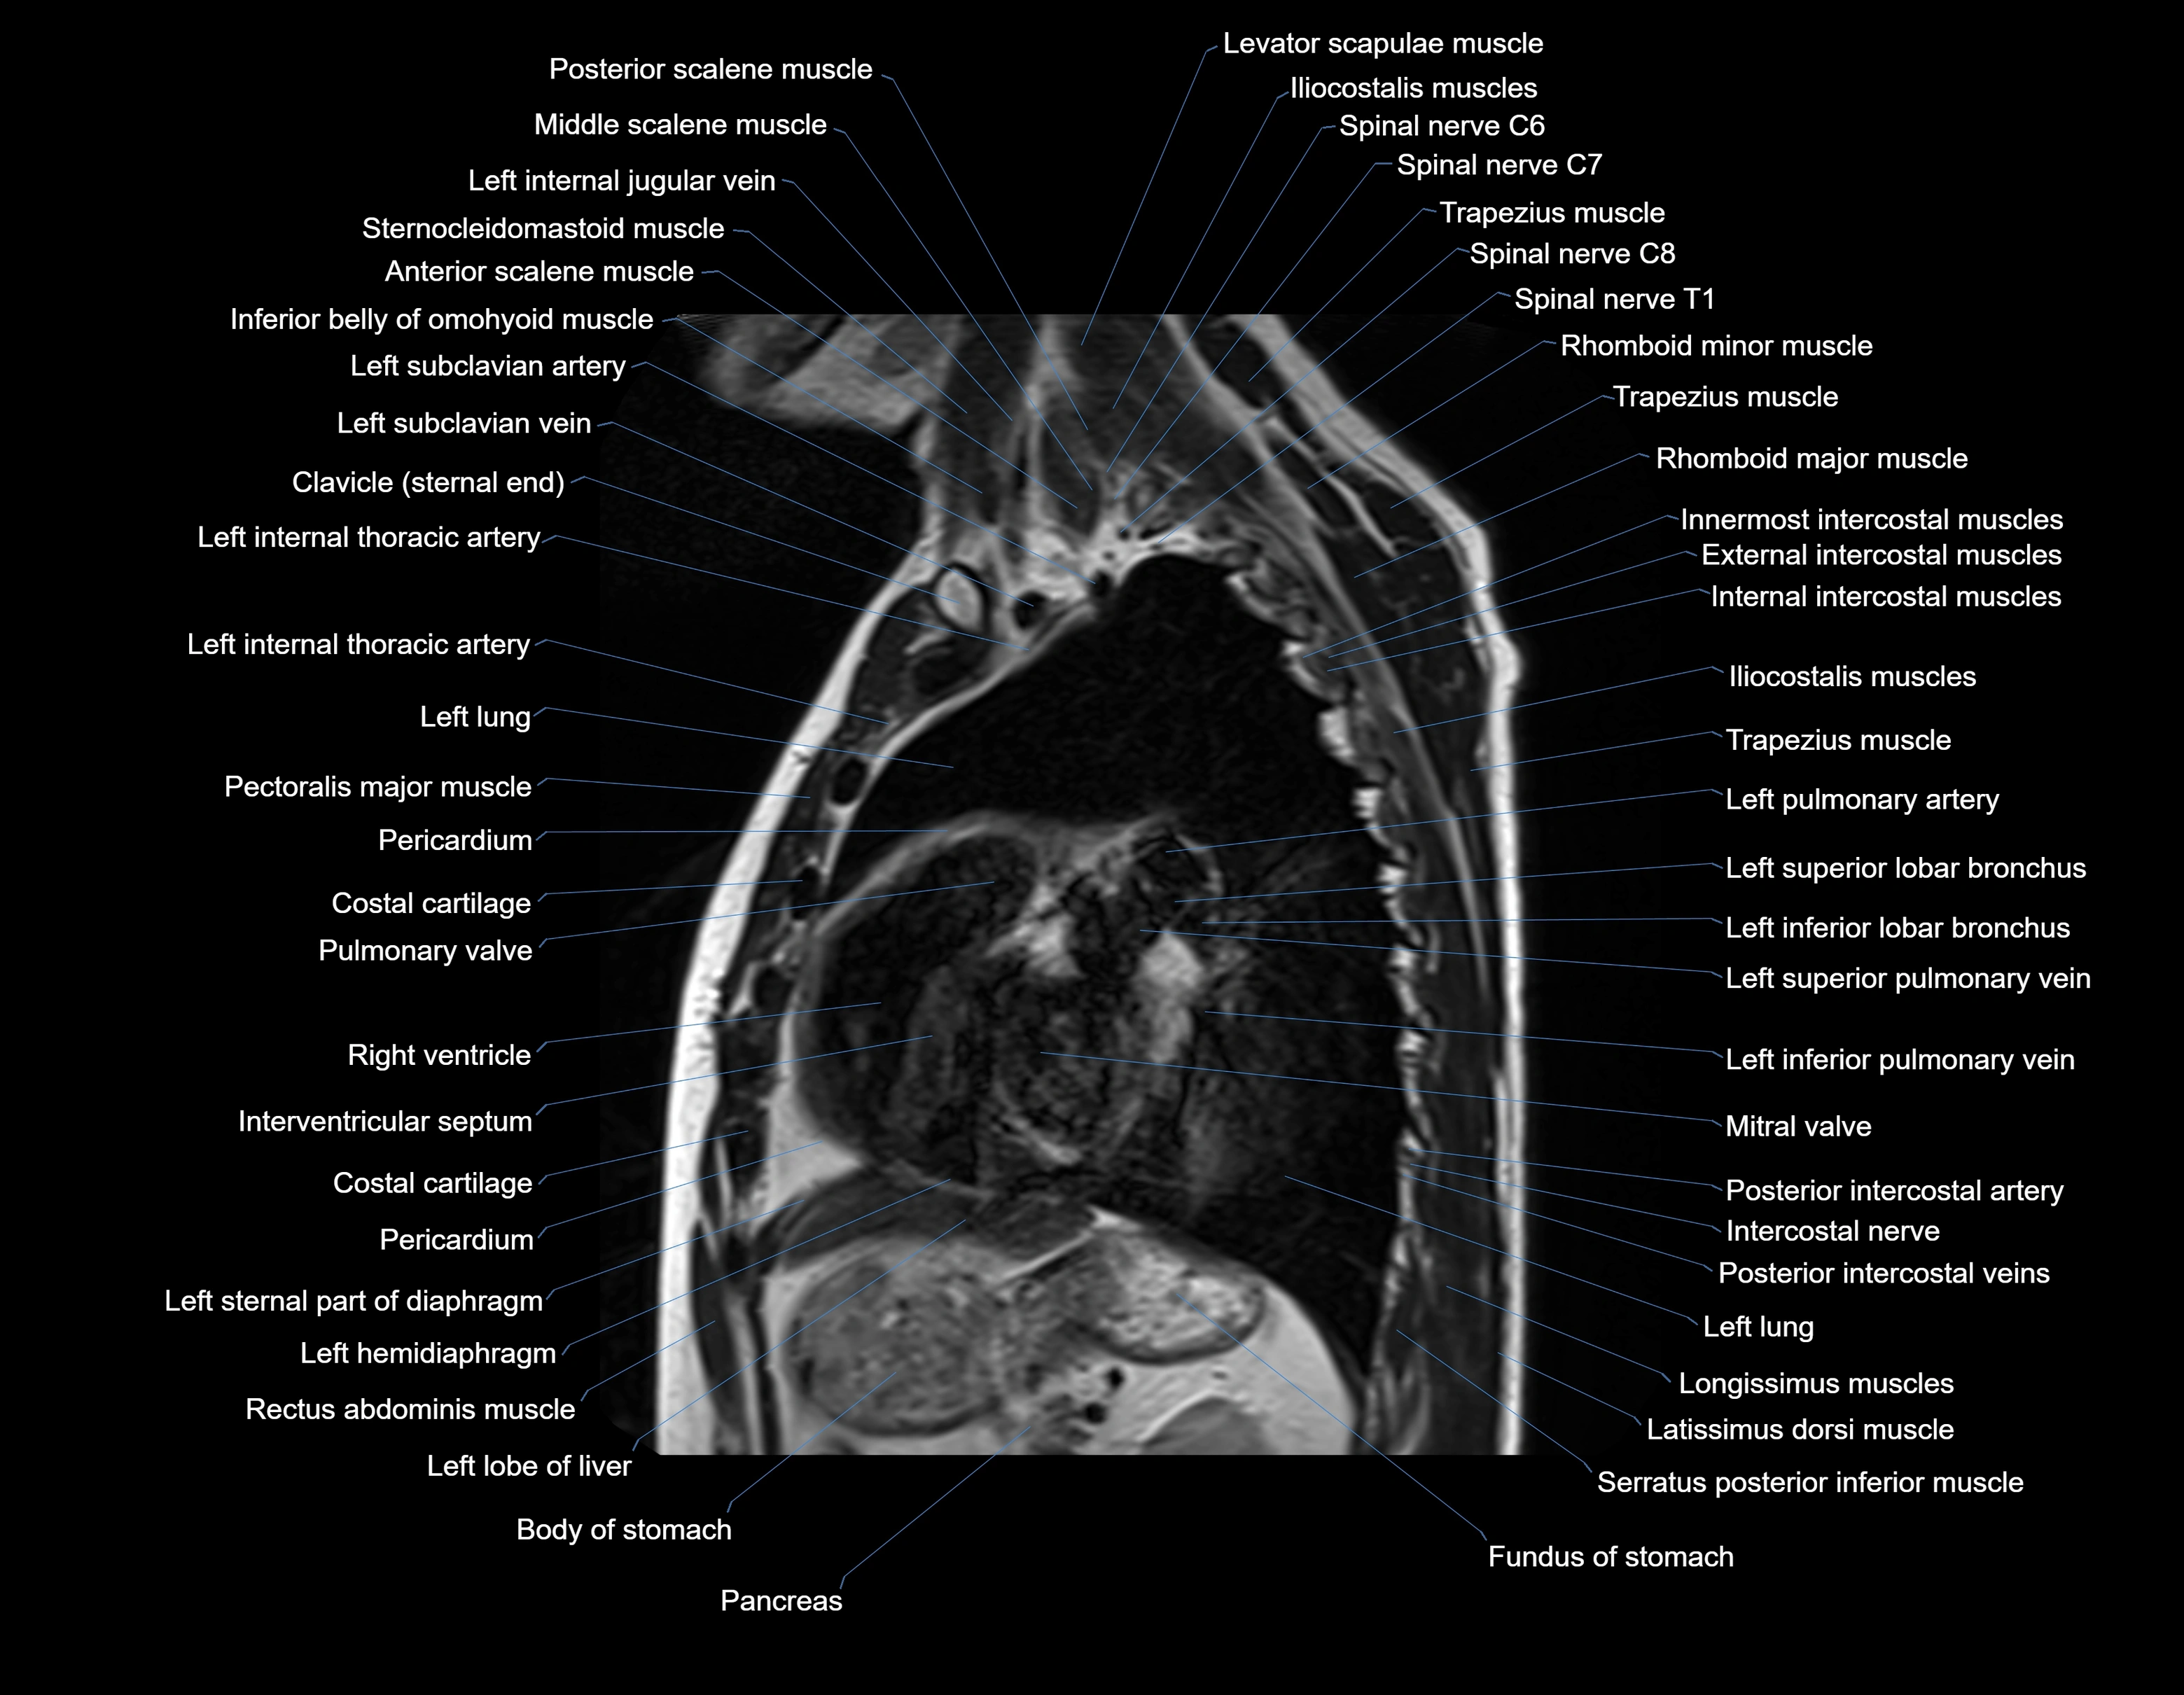

MRI images